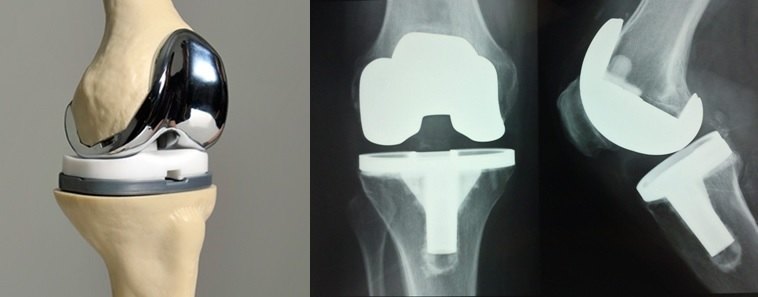

12.对于年龄大于65岁;晚上疼痛,难以入睡;以及因为关节疼痛无法出门,生活质量极差的骨关节炎患者(图1e)可以考虑关节表面置换(去除磨损的关节表面,以金属的假体表面覆盖关节表面,中间置入耐磨的聚合物垫片,从而不再骨头磨骨头,减除关节活动时的疼痛)(图15)。

图15.膝关节表面置换。